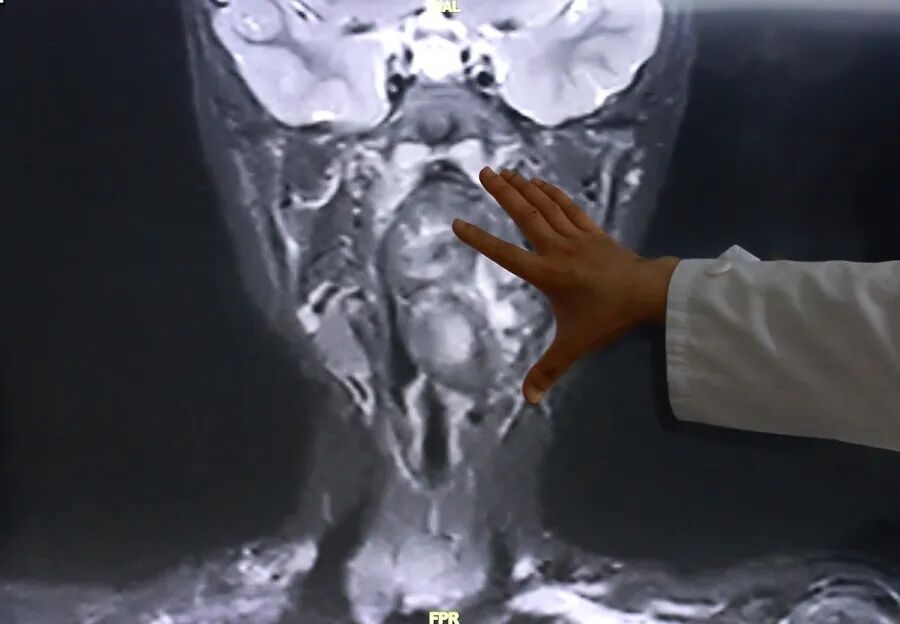

接诊后,综合前期检查及患儿家长自述病情,复旦儿科专家团队高度重视气道梗阻风险,立即启动复杂气道疾病绿色通道,完善增强CT及磁共振检查,明确小亮所患的肿瘤约7厘米×3.5厘米×3厘米,犹如“拳头”般大小。

专家表示,该肿瘤紧邻颈内动静脉并将血管明显向外推移,肿瘤向咽喉腔内隆起,占据大部分口咽及下咽腔,严重压迫声门,随时可能发生窒息。

复旦大学附属儿科医院耳鼻咽喉头颈外科副主任陈超表示,“我们可以看出它有脂肪,有软骨,这是一对双胞胎,一个是我们正常发育成的人,另外一个‘他’可能残留在这个咽旁间隙里面,就发育成了这样的一个畸胎瘤。”

陈超还表示“6岁男孩的口咽腔大概在8厘米左右,这个孩子的肿瘤已经高达6厘米多,整个气道已经完全被这个膨大的肿瘤占据了,只有一条黑颜色的线,这是它透气的空间,再让它继续膨胀下来,首先出现的症状应该是呼吸道的梗阻窒息,会出现孩子窒息致死的可能。”